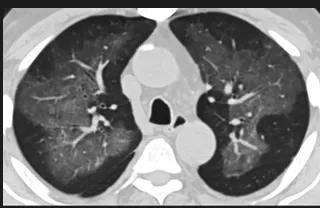

更值得注意的是,有之前应对过武汉新冠疫情的中国权威肺病专家,在查阅了60篇涉及美国“电子烟肺病”病例的研究论文,并对其中142位电子烟肺病患者的250张肺部影像图片、临床信息以及文献原文进行了仔细全面的研究后,发现这些病例中有16个更有可能是新冠肺炎的“疑诊患者”,有5个临床症状和治疗情况相对完整的患者,还被这些专家认定为了“中度可疑”。另外,这16个病例中有12个病例的发病时间,都在2020年以前。

新冠病毒是否来自美国?迄今为止最全面的线索来了

(这4张图,是专家怀疑被误诊为电子烟肺病的其中一个病例的肺片。专家表示,他们不是仅仅通过一张影片做判断的,而是通过这4张涵盖了这名病例肺部多天变化情况的影片进行的研判,认为该病例的病程进展跟新冠更为相似)